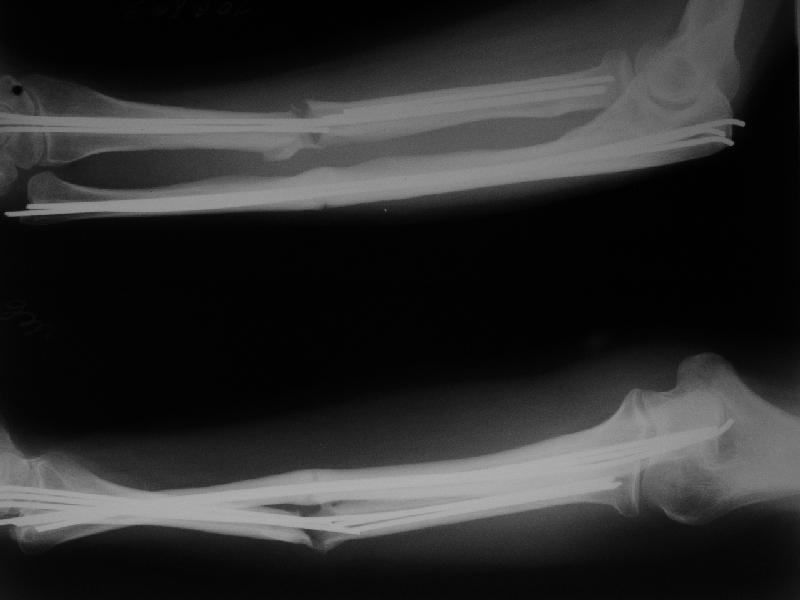

Уважаемые коллеги, Госпитализирована женщина, 31 год. Травма 26.09.06. Бытовая, упала. Оперирована в одной из горбольниц открыто, пучками спиц. 1 месяц в гипсе.

Подвижность усилилась примерно в 2 мес. (видимо, перелом спиц в лучевой кости). Движения в локтевом суставе N, ротация хорошая (подвижность лучевой кости), в кистевом тыльная 5-10 гр, ладонная 30гр. Обсуждаем варианты реостеосинтеза. Спицы удаляем все, при удалении из центрального отломка лучевой без вскрытия кости в области перелома не обойтись. Если восстановить ось и длину лучевой кости, получается дефект ~1,5-2 см. Замещать дефект удлинением одого из отломков в аппарате? Долго, и функция кисти и пальцев может еще ухудшиться.Поэтому думаем про укорачивающую резекцию обеих костей, локтевой чуть больше, остеосинтез пластинами, наверно, LCP. Блокируемый интрамедуллярный остеосинтезтоже доступен, но есть ли тут у него преимущества? Или есть смысл попытаться не трогать локтевую, а заместить дефект лучевой аутотрансплантатом из крыла? Или резецировать головку локтевой? Какие вариант и почему тут предпочтителен, на Ваш взгляд? Спасибо!Александр Виноградский клиника травматологии УНИИТО

1. У этой пациентки кость в принципе срастается, т.е. остеогенез не подавлен - периостальная реакция. Т.е. складывается впечатление, что кость хотела срастись, но ей не дали. Не создали словий. Скорее всего - из-за нестабильного остеосинтеза и несостоятельнйо гипсовой иммобилизации (видимо, виновата ротация). Отсюда вывод - создать эти условия. Для этого:

В подобном случае мы бы заместили дефект лучевой кости аутотрансплантатом из крыла подвздошной кости, при дефекте свыше 4-5 см - несвободным, с фиксацией способом КНО (комб.напряженный остеосинтез) или используя блокируемый остеосинтез. Вместо представленной на рис. опоры может быть использована монолатеральная на основе 2-х 4 мм стержней-шурупов